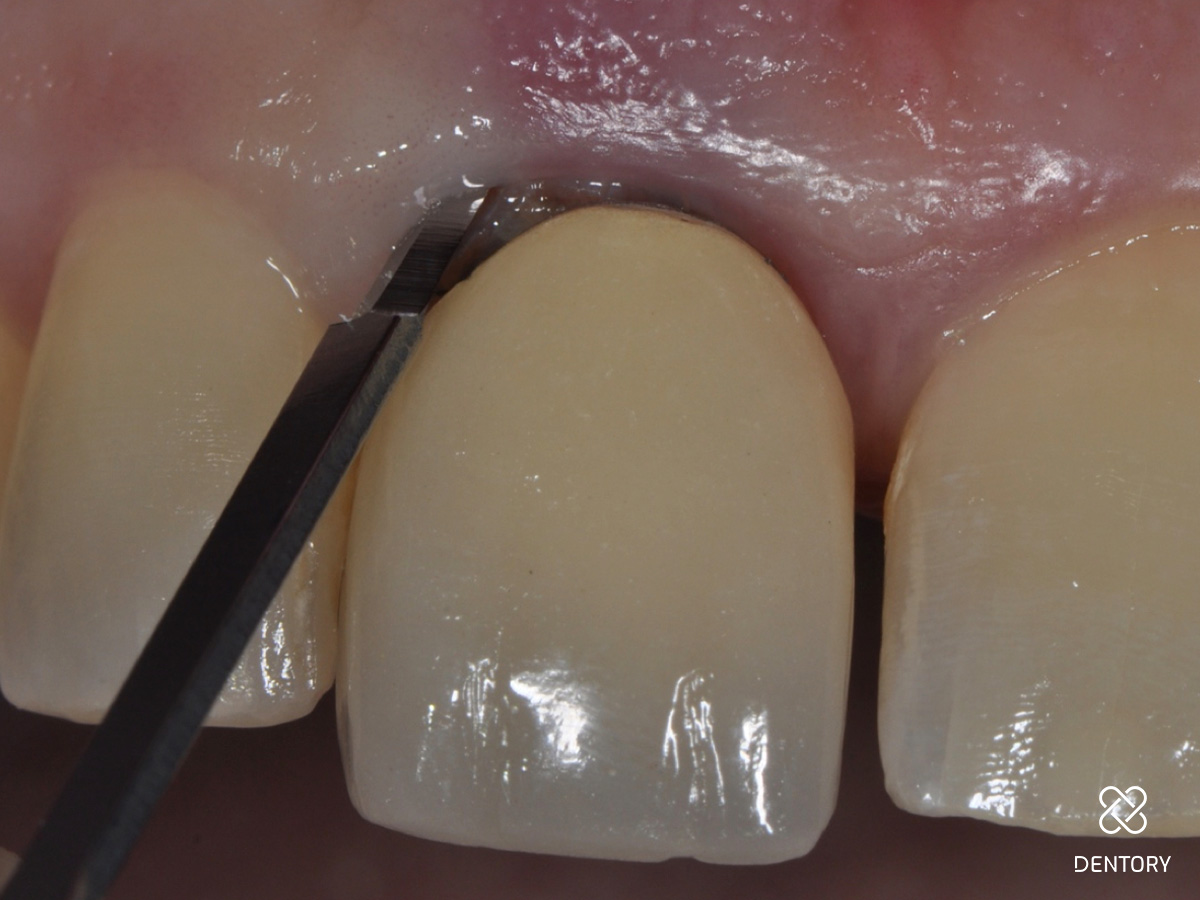

Abbildung 9

Das Transplantat sollte im Durchmesser etwa 1mm breiter als die Extraktionsalveole sein